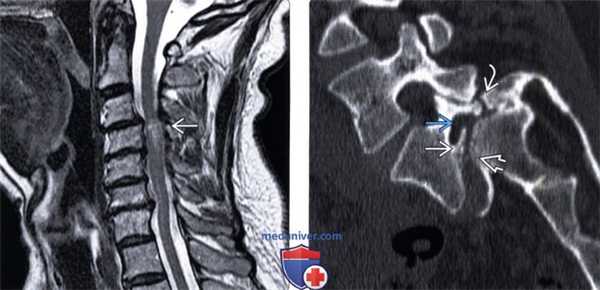

(Слева) Т1-ВИ, сагиттальная проекция: несвежий дефект межсуставной части дуги, характеризующийся нормальным сигналом жировой ткани костного мозга. На уровне L5-S1 видны признаки выраженного фораминального стеноза. Обратите внимание на нормальный низкоинтенсивный сигнал интактной межсуставной части дуги L4, зона которого может напоминать дефект.

(Справа) Т1-ВИ, сагиттальная проекция: дефект МЧ дуги L4. Переломы МЧ на этом и вышележащих уровнях встречаются гораздо реже, чем на уровне L5.

(Слева) Т2-ВИ, сагиттальная проекция: признаки многоуровневого спондилеза шейного отдела позвоночника с антеролистезом СЗ позвонка, стенозом спинномозгового канала на этом уровне и компрессией спинного мозга. На уровне стеноза видны признаки миеломаляции спинного мозга, развившейся на фоне постоянной травматизации его в условиях стенозироваиного канала и проявляющейся усилением Т2-сигнала.

(Справа) КТ, сагиттальный-срезе (костный режим): задний край тела L5 находится практически на одном уровне с передним краем S1. Хорошо виден дефект межсуставной части дуги, а также признаки выраженного стеноза межпозвонкового отверстия.